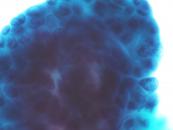

第35回日本臨床細胞学会九州連合会学会(宮崎)スライドカンファレンス症例4

種別:婦人科

出題:熊本大学病院 病理診断科・病理部 佐野直樹 先生

| 年齢 | 60歳代 | 性別 | 女性 |

| 採取部位 | 子宮頸部 | 採取方法 | 擦過 |

既 往 歴:糖尿病、脂質異常症

現 病 歴:4年前に帯下の増加を自覚し受診し、子宮頸部細胞診でNILMの判定。今回、下腹部痛を主訴に受診し、腟鏡診では病変は不明瞭だったが、双合診で子宮頸部全体に硬結あり。

| 正解 | 5.胃型粘液性癌 |

▼選択肢及び投票結果

| 1.化生細胞および修復細胞 | 3件 | (3.1%) | |

| 2.重層性粘液産生上皮内病変(SMILE) | 38件 | (39.2%) | |

| 3.通常型腺癌 | 10件 | (10.3%) | |

| 4.明細胞癌 | 26件 | (26.8%) | |

| 5.胃型粘液性癌 | 20件 | (20.6%) | |

| 投票総数 | 97件 | (100%) |